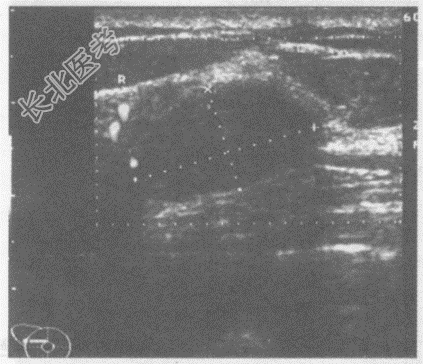

- 单项选择题临床资料:女, 21岁,自述洗澡时无意中发现右乳腺肿物。

临床物理检查: 右乳腺可扪及一肿物,活动度好, 边缘光滑。

超声综合描述:右乳外上象限可见1.9cm×1.1cm椭圆形低回声区, 形态规则,纵横比值<1, 边界光滑清晰,可见完整包膜, 内回声均匀,探头加压前后径稍减小, CDFI:低回声区周边可见血流信号。

超声提示:  A、右乳腺增生结节

B、右乳腺纤维腺瘤

C、右乳腺脓肿

D、右乳腺癌

E、乳腺结核